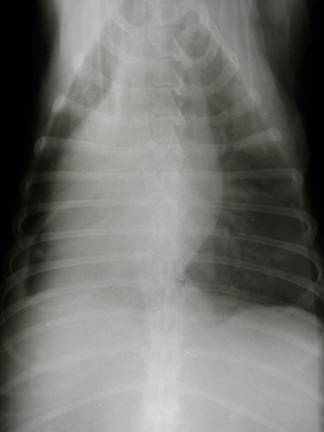

Röntgen: |

Flüssigkeitsansammlung im Thorax (rote Pfeile) und vergrößerte Herzsilhouette |